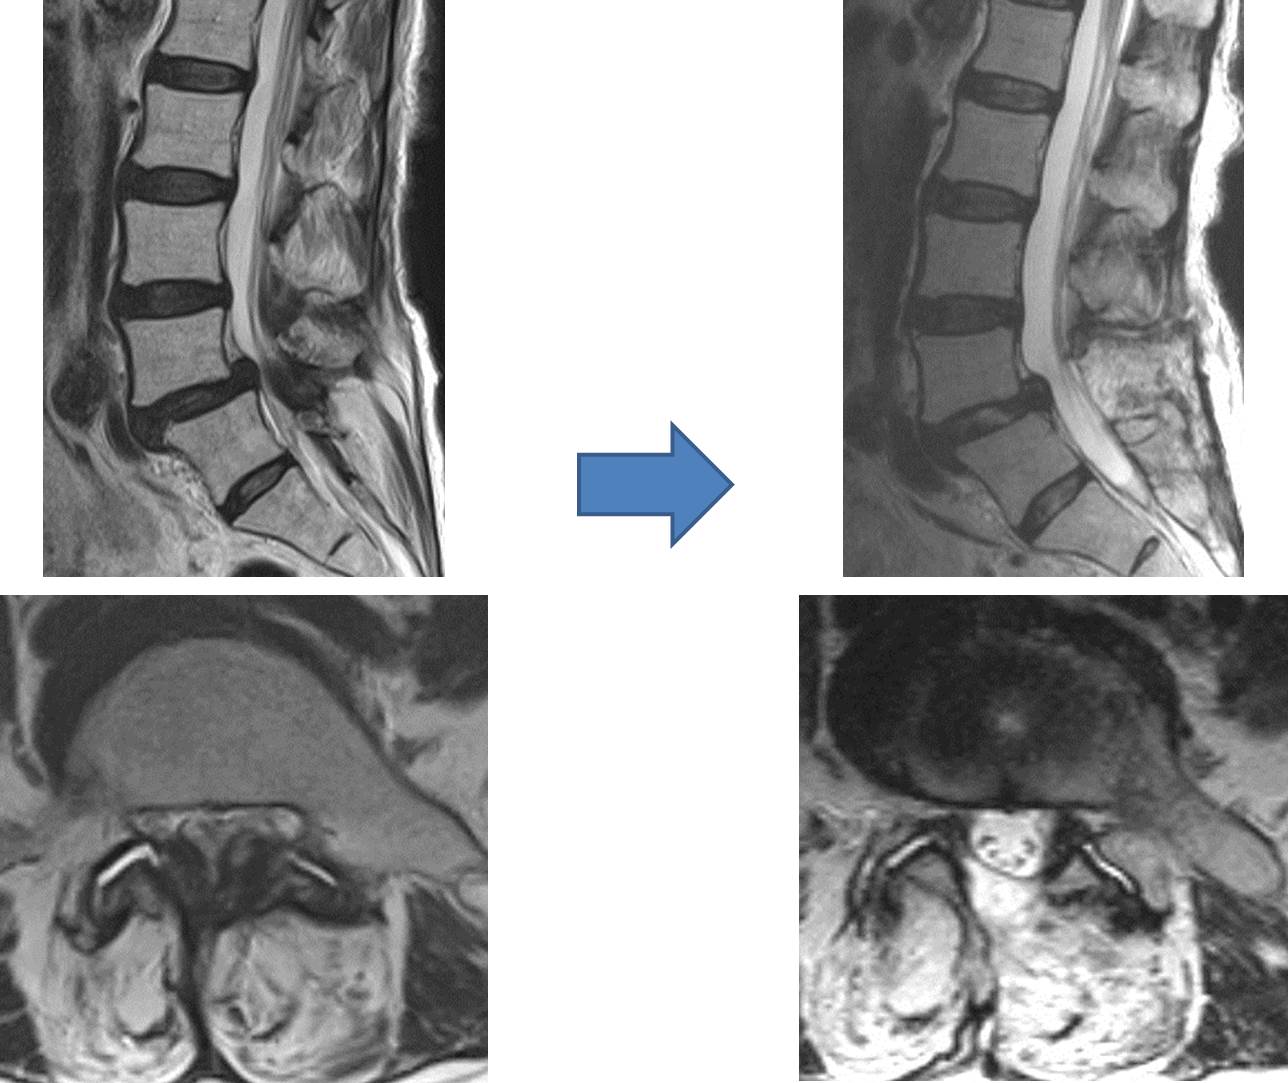

背骨の前部に存在する椎体の間に存在し、衝撃を吸収する役割を担っている軟骨組織が椎間板です。突然の外力や長期間の腰部に蓄積された負担により、椎間板の周囲を構成している線維輪と呼ばれる組織に裂隙が生じ、内部の髄核と呼ばれる組織が後方に突出、脱出する事で疼痛が出現します。

突出した髄核が神経組織を圧迫すると、腰部、下肢への疼痛、しびれ感などの症状が出現します。症状が軽度である場合には、投薬、安静(外固定を含め)、牽引などによる治療が行われますが、四肢・手足の麻痺、排尿・排便の障害、耐えられない疼痛、しびれ感などを認めた場合には、可及的早期の外科治療が必要となります。